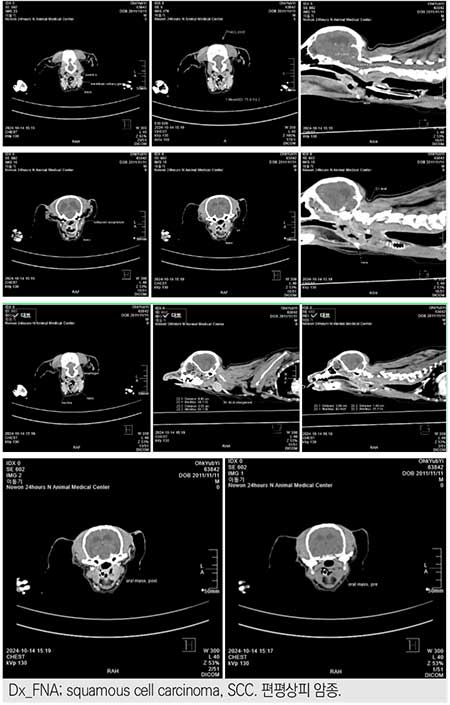

흉부 및 복부 방사선 검사 결과, 인두 부위에 연부 조직 음영이 관찰되었고, 이에 따라 인두 종양의 가능성을 의심하여 추가 진단이 이루어졌다. FNA 결과, 인두 부위에 편평상피암종(SCC)이 확인되었고, 종양 제거를 위한 Cryo-surgery를 수행하였다. 본 사례는 Cryo-surgery의 효과와 예후를 살펴봄으로써 편평상피암종 치료에서의 임상적 적용 가능성을 논의하고자 한다.

인두(pharynx): 정상적인 공기 음영이 소실되고, 연부조직 음영이 확인된다. 이는 인두 부위에 조직이 밀집되어 공기가 부족해졌다는 것을 의미하며, 혹시 인두 종양이나 염증성 병변이 있을 가능성을 염두에 두어야 한다.

Pharyngeal Mass(인두 종양): 흉부 방사선 검사에서 관찰된 인두 부위의 공기 음영 소실과 연부조직 음영을 바탕으로 인두 부위에 종양이 있을 가능성을 고려한다. 추가적인 진단(CT 스캔 또는 조직 검사)이 필요할 수 있다.